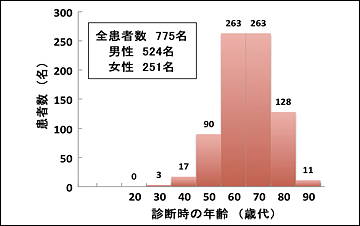

2007~2011年の5年間に当院において診療した肺がん患者の総数は775名(男性524名、女性251名、平均年齢70.8歳)でした(図1)。検査の結果から全患者の約34%が早期肺がんでしたが、残りの66%は進行肺がんと診断されました(図2)。775名中246名(全体の32%)が手術療法(外科的切除術)を受けました。手術を受けた患者のうち41名(手術患者の17%)は再発予防の抗がん剤投与による追加治療を受けました。残りの529名(68%)は、抗がん剤治療、放射線治療、緩和治療を単独または組み合わせて治療を行いました。手術療法を受けた患者と受けなかった患者の病期内訳を、それぞれ(図3)のA、Bに示しました。

図1 当院肺がん症例における年代別患者数(2007~2011年)